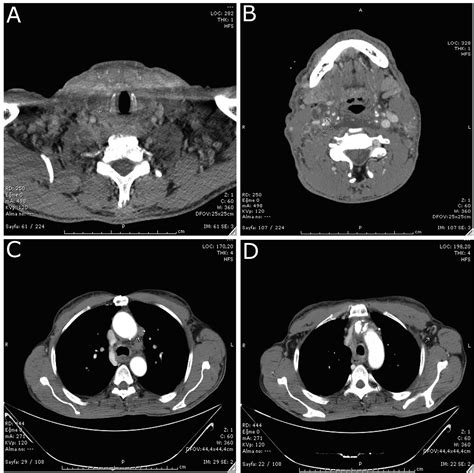

Diagnostic Approaches and Staging

Accurate diagnosis is the cornerstone of effective management. Physicians utilize a combination of imaging and molecular testing to map the extent of the disease. Because thyroid cancer can be slow-growing, imaging plays a vital role in monitoring how the cancer behaves over time.

Ultrasound Used to examine the primary tumor and suspicious lymph nodes in the neck.

PET/CT Scan Helps locate metabolic activity in areas where the cancer may have spread.